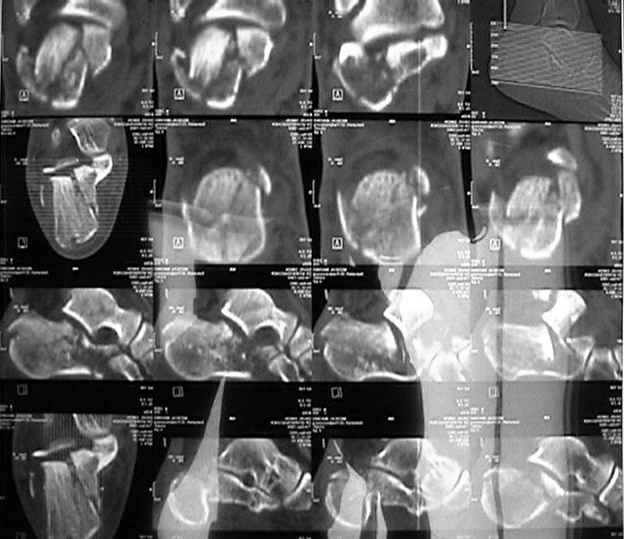

На этой неделе оперировали. КТ наши рентгенологи сделали зачем-то горизонтальной плоскости, поэтому не привожу. Сделали открытую репозицию, заполнили дефект трансплантатом из крыла подвздошной кости.

После удаления спиц положение фасетки немножко ухудшилось. Такие дела. Жду комментариев.

Судя по вашим рентгенограммам, восстановить суставную поверхность таранно-пяточного и пяточно-кубовидного сустава полностью не удалось, хотя угол Белера выглядит гораздо лучше, чем на предоперационной рентгенограмме,

что решает проблему посттравматического плоскостопия, восстановлена длина пяточной кости. Жаль, что возникла проблема с качеством томогафии. Интересно было бы знать, на сколько фрагментов была *расколота* суставная фасетка

подтаранного сустава( в мной оперированных случаях наиболее часто встречалось 2, реже 3 фрагмента) Несмотря на вколоченный характер перелома, после выполнения репозиции костной пластикой я не пользуюсь и ни в одном из случаев не наблюдал коллапса пяточной кости, по-видимому можно объяснить хорошими местными регенеративными возможностями.

В данном случае восстановлена лишь ось пятки - угол Белера в боковой проекции и смещение кнаружи и по длине в прямой. Гораздо проще и с несравнимо меньшим риском этого можно остигнуть, применив внешний остеосинтез.

Суставная поверхность не восстановлена, внизу (по подошвенной поверхности) - большой фрагмент. Зачем тогда шли открыто? Как мягкие ткани? Довольно самокритично звучит - но больному выполнили дорогостоящее исследование (КТ), а не сказали рентгенологам, в какой проекции делать. Жалко.